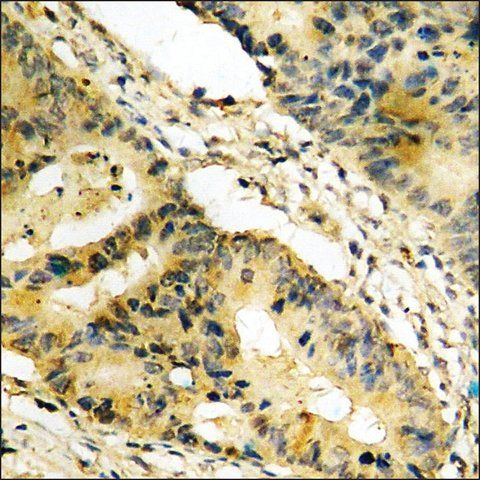

| technique(s) | ELISA: 1:5000 immunohistochemistry: 1:50-1:100 western blot: 1:500-1:1000 |